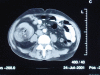

Ileocolic Intussusception - A rare cause of acute intestinal obstruction in adults; Case report and literature review

Colonic Intussusception although common in children, is a rare cause of acute intestinal obstruction in adults. The etiology, clinical presentation and management of this condition is different in adults as compared to children. Pre-operative diagnosis is usually difficult due to the non specific and intermittent nature of the symptoms. CT scan can be a helpful adjunct in establishing the diagnosis. We present a case report of adult ileocolic intussusception with classical radiological signs and operative findings. A brief literature review is also presented with emphasis on the controversy of reduction of the intussusception before resection.